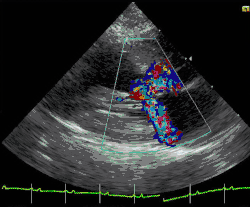

Farbdopplerdarstellung einer HOCM bei einer Katze

Bei Katzen ist die hypertrophe Kardiomyopathie die am häufigsten beobachtete Form der Erkrankung. Sie wird auch als Folgeerscheinung einer Schilddrüsenüberfunktion beobachtet (thyreotoxische Kardiomyopathie). Eine Sonderform gleicht der hypertroph-obstruktiven Kardiomyopathie des Menschen. Daneben sind auch die restriktive und die dilatative Kardiomyopathie bei Katzen beschrieben. Letztere wird aber als sekundäre Kardiomyopathie eingestuft, da sie die Folgeerscheinung eines Mangels an dem für Katzen sehr wichtigen Taurin ist. Da industrielle Fertigfuttermittel mit diesem Inhaltsstoff angereichert sind, wird diese Form der Erkrankung bei Katzen zunehmend seltener beobachtet. Weiterhin existieren Übergangsformen, die sowohl Zeichen einer Erweiterung als auch Zeichen einer Hypertrophie zeigen. Sie werden als intermediäre Kardiomyopathie bezeichnet. Katzen mit einer Herzerkrankung haben ein hohes Risiko für eine arterielle Thromboembolie.[13]